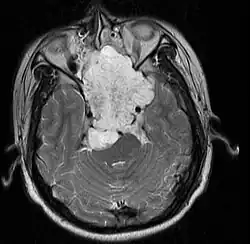

MRI of extensive clival chordoma in 17-year-old male patient, axial view. Tumor in the nasopharynx extending from nasal cavity to brainstem posteriorly is clearly visible.